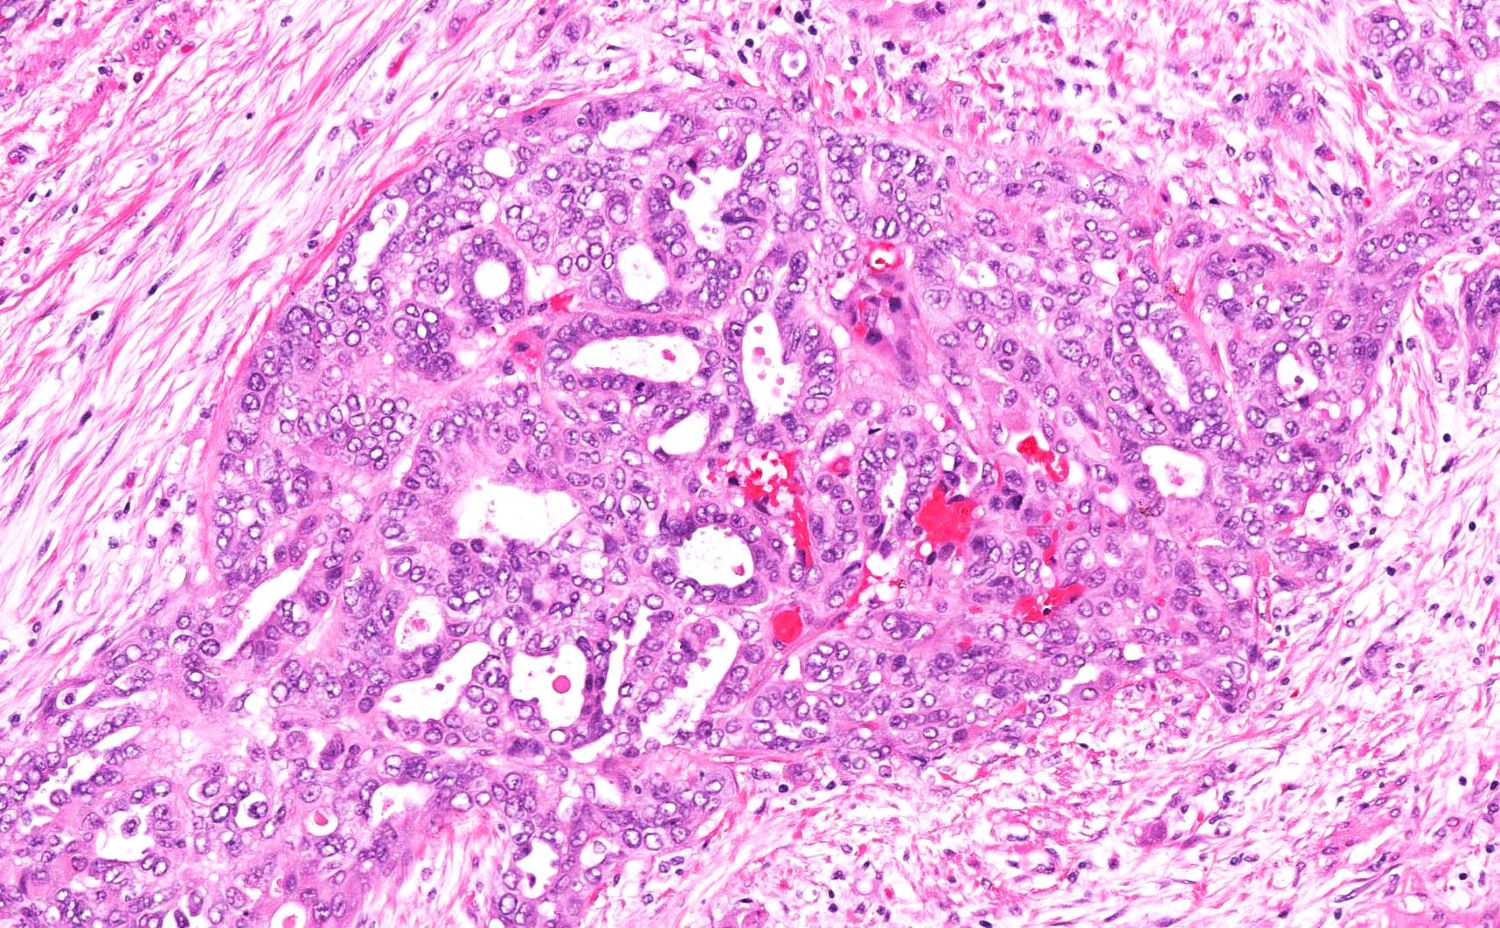

- Variety of histologic patterns that may be present within the same tumor

- Most frequently small tubules with ductal / glandular growth

- Papillary, solid growth, trabecular, retiform, sex cord-like, sieve-like, glomeruloid and spindle cell areas have all been described

- Luminal eosinophilic secretions are characteristic but not always identified

- Tumor cells can be flattened, cuboidal or columnar with mild to moderate cytological atypia

- Clear cell features can be seen but are less common

- High grade cytological atypia is usually not a predominant feature

- Nuclei show vesicular chromatin and nuclear grooves

- Sarcomatoid transformation has been seen in rare instances

- Squamous, ciliated or mucinous differentiation (metaplasia) are not present and there are no associated mesonephric remnants (J Clin Med 2021;10:698)

Microscopic (histologic) images

Contributed by Daniel Graham, M.D., Adele Wong, M.B., B.Ch., B.A.O. and Lucy Ma, M.D.